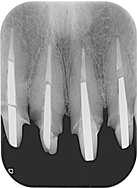

治療前,X光片及口內照片。

右上側門牙及左上正中門牙斷裂。

舊牙冠拆除後,舊牙冠拆除後,術後X光片。